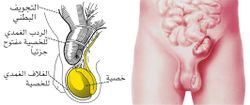

الفتق الإربي

يظهر الفتق الإربي من خلال الفوهة الإربية والتي يمر فيها الحبل المنوي عند الذكور والرباط المدور المعلّق للرحم عند الإناث، وقد يكون ولادياً بسبب بقاء ما يُعرف بالاستطالة التناسلية (وهي ممر تعبر من خلاله الخصية من البطن إلى الصفن في نهاية الحياة الجنينية) وذلك عند الذكور أو بقاء قناة نك عند الإناث. هذا الفتق هو الأكثر شيوعاً من حيث نسبة الظهور. ويحدث عند الذكور بنسبة تزيد قليلاً على حدوثه عند الإناث.

الفتق الإربي المغبني

مقالة مفصلة: فتق إربي مغبني

إذا ظهر هذا الفتق بمرحلة متأخرة من العمر يكون سببه ضعف العضلات في منطقة مثلث هسلباخ Hesselbach، وهي تناسب تشريحياً مكان الفوهة الإربية الظاهرة.